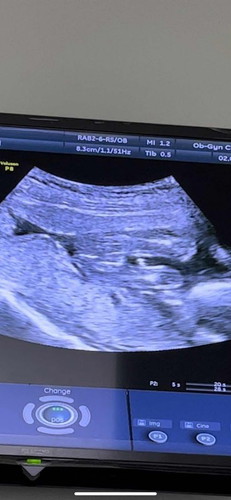

แม่ๆช่วยดูหน่อยได้ไหมคะ ว่าเป็นเพศชายหรือเพศหญิง

พอดีไปซาวด์น้องไม่ค่อยให้ความร่วมมือค่ะ ภาพชัดสุดเลยได้แบบนี้ อยากถามจากประสบการณ์ของแม่ๆแต่ละคนค่ะ ลุ้นๆๆ ตื่นเต้นค่า🥰 17W6D #ทีมกันยายน #ท้องแรก #ขอคำแนะนำหน่อยค่ะ #ขอบคุณสำหรับคำตอบค่ะ